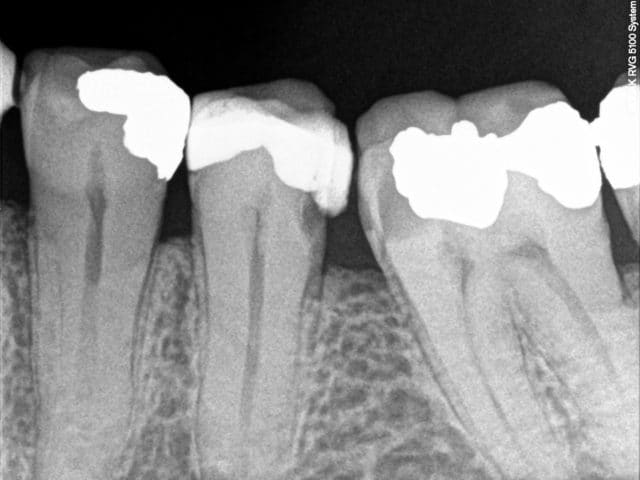

Pour ce qui est de la possibilité de manipuler une radio, un confrère c'est fait prendre au début de la généralisation de la RVG.

Modification;

" l'affaire est assez vielle puisque cela avait été découvert lors des demandes d'entente préalable par le fait que les radios étaient trop parfaite tout le temps ce qui avait éveillé à l'époque les dentistes conseils."

Le problème enki, c'est que la qualité, tu la fais pour toi principalement. Car nombre de patients ne la voient pas et que pour ce qui est des contrôles, c'est plus la statistique qui compte devant la qualité. Pour rappel, ce qui a choqué les dentistes conseil dans l'affaire que je te cite, c'est la trop grande qualité des endos sur les radios envoyées.